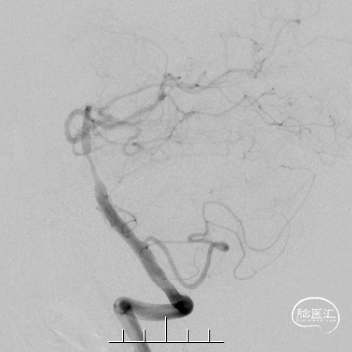

术前DSA影像信息

病变部位:基底动脉

狭窄率:90%

狭窄长度:19.1mm

参考远端血管直径:3.58mm

术前

术后

6个月随访

18个月随访